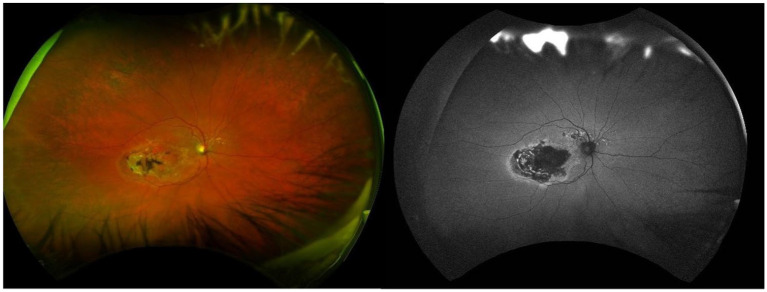

Charles Bonnet syndrome (CBS) is characterised by visual hallucinations in individuals with significant visual impairment. This literature review and case report focus on the unique presentation of CBS in an 82-year-old woman with age-related macular degeneration, who experienced visual hallucinations for over 10 years. The aim is to raise awareness of CBS among healthcare professionals and the public, addressing the diagnostic challenges that contribute to its underdiagnosis and mismanagement. A literature review was conducted to assess the prevalence and diagnosis of CBS. Databases including Google Scholar and PubMed were searched using the terms 'Charles Bonnet Syndrome', 'Case report' and 'Diagnosis'. The patient reported a range of visual hallucinations, from simple geometric shapes to highly detailed figures. A diagnosis of CBS was made based on her visual impairment and the nature of the hallucinations. No treatment was required, and the patient was reassured that the hallucinations were benign and unrelated to any psychiatric or neurological disorder. This case highlights the diagnostic challenges associated with CBS, which is often misdiagnosed or overlooked due to its rarity and the hesitancy of patients to disclose their symptoms. The long period of unreported hallucinations in this case emphasises the need for greater awareness among healthcare providers, enabling earlier recognition of CBS and differentiation from other conditions. The wide range of hallucination types seen in CBS adds to the complexity of the syndrome. The key takeaway is that increased awareness and recognition of CBS are essential for proper diagnosis, reducing patient anxiety and avoiding unnecessary treatments. This case contributes to the existing literature by illustrating the broad spectrum of CBS presentations and advocating for enhanced education on the condition.